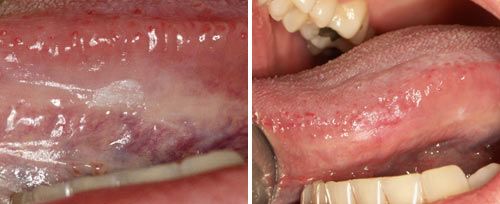

Oral Surgery

Clinical Results